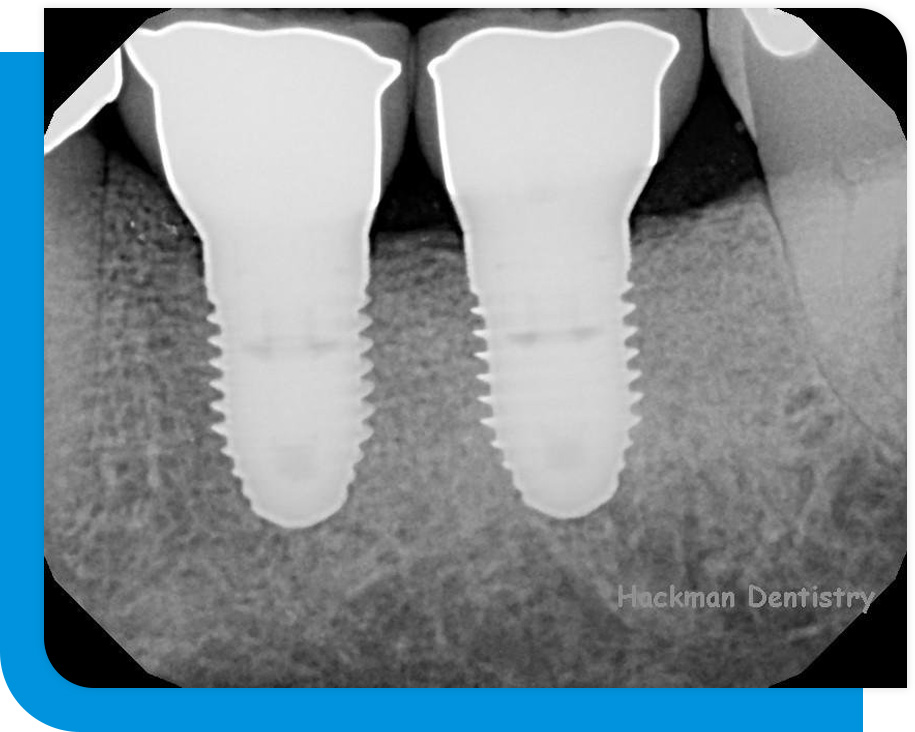

A sizable portion of the dental business is rapidly adopting digital dental x-rays. The dentist can use a digital x-ray to capture an image of the tooth or teeth and upload it to an imaging program. There are several features in this imaging package that will enable the dentist to examine the teeth and associated structures up close and with astounding accuracy.

The digital x-ray also offers the patient over 90% less radiation than a traditional x-ray. This is because the digital x-ray, which was created expressly with the patient in mind, is considerably more sensitive to this radiation.